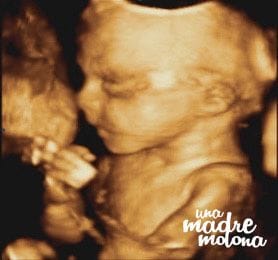

Y sin más dilación, os presento a ¡¡¡Minimolona!!!

¿No os parece increíble lo bien que se ve? marido y yo (bueno, y el resto de la familia molona) babeamos sin parar 😀 La chiquitina se pasó media sesión jugando con el cordón umbilical, lo cogía, se lo metía en la boca, lo volvía a soltar… ¡se mueve muchísimo!